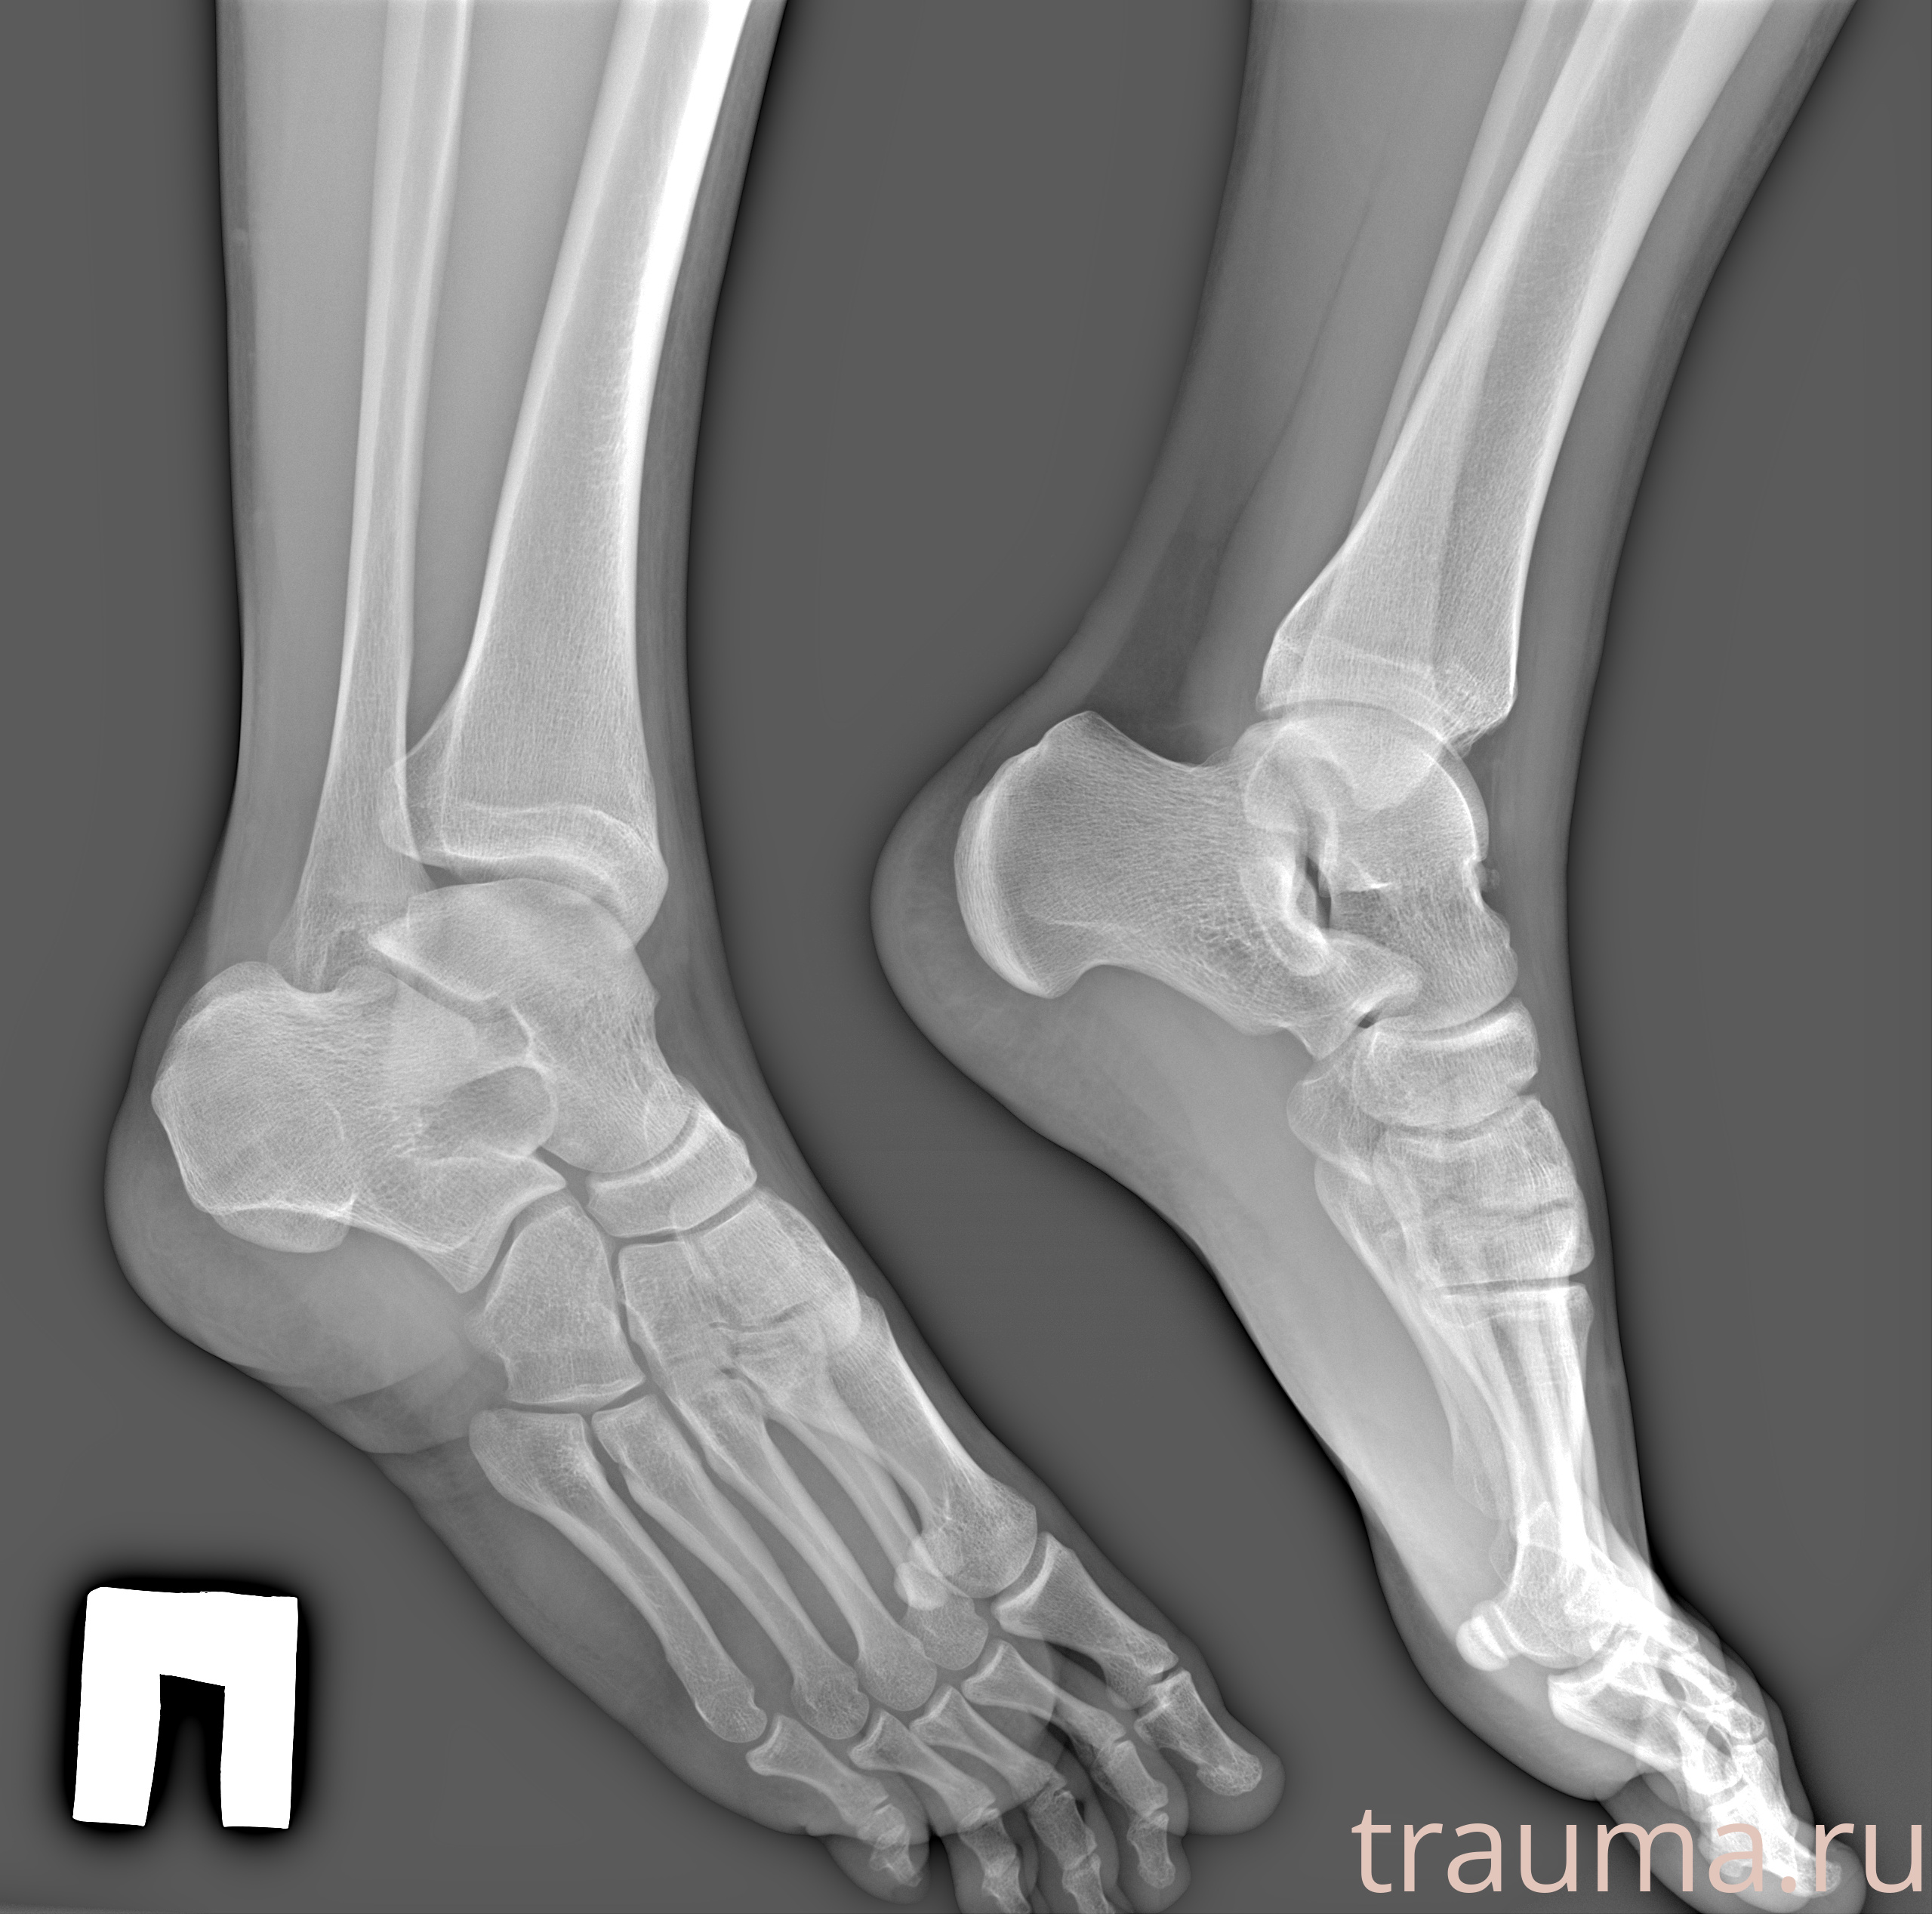

Рентгенограммы